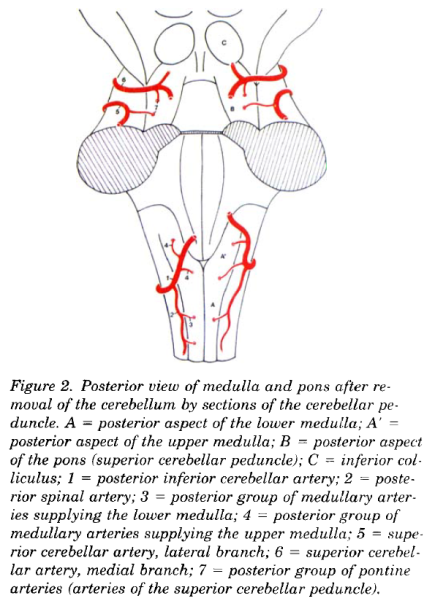

Cerebral vascular territories

Brainstem